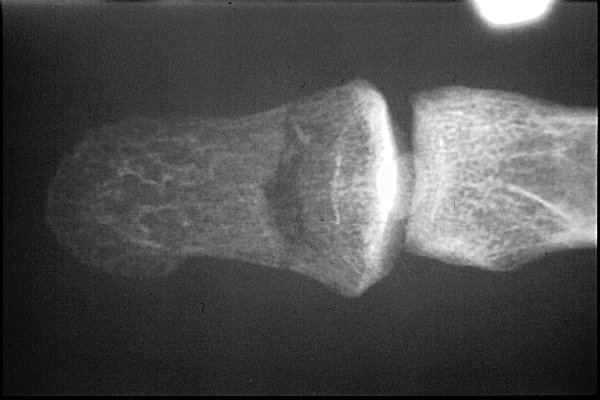

Return to Nail Bed Fracture